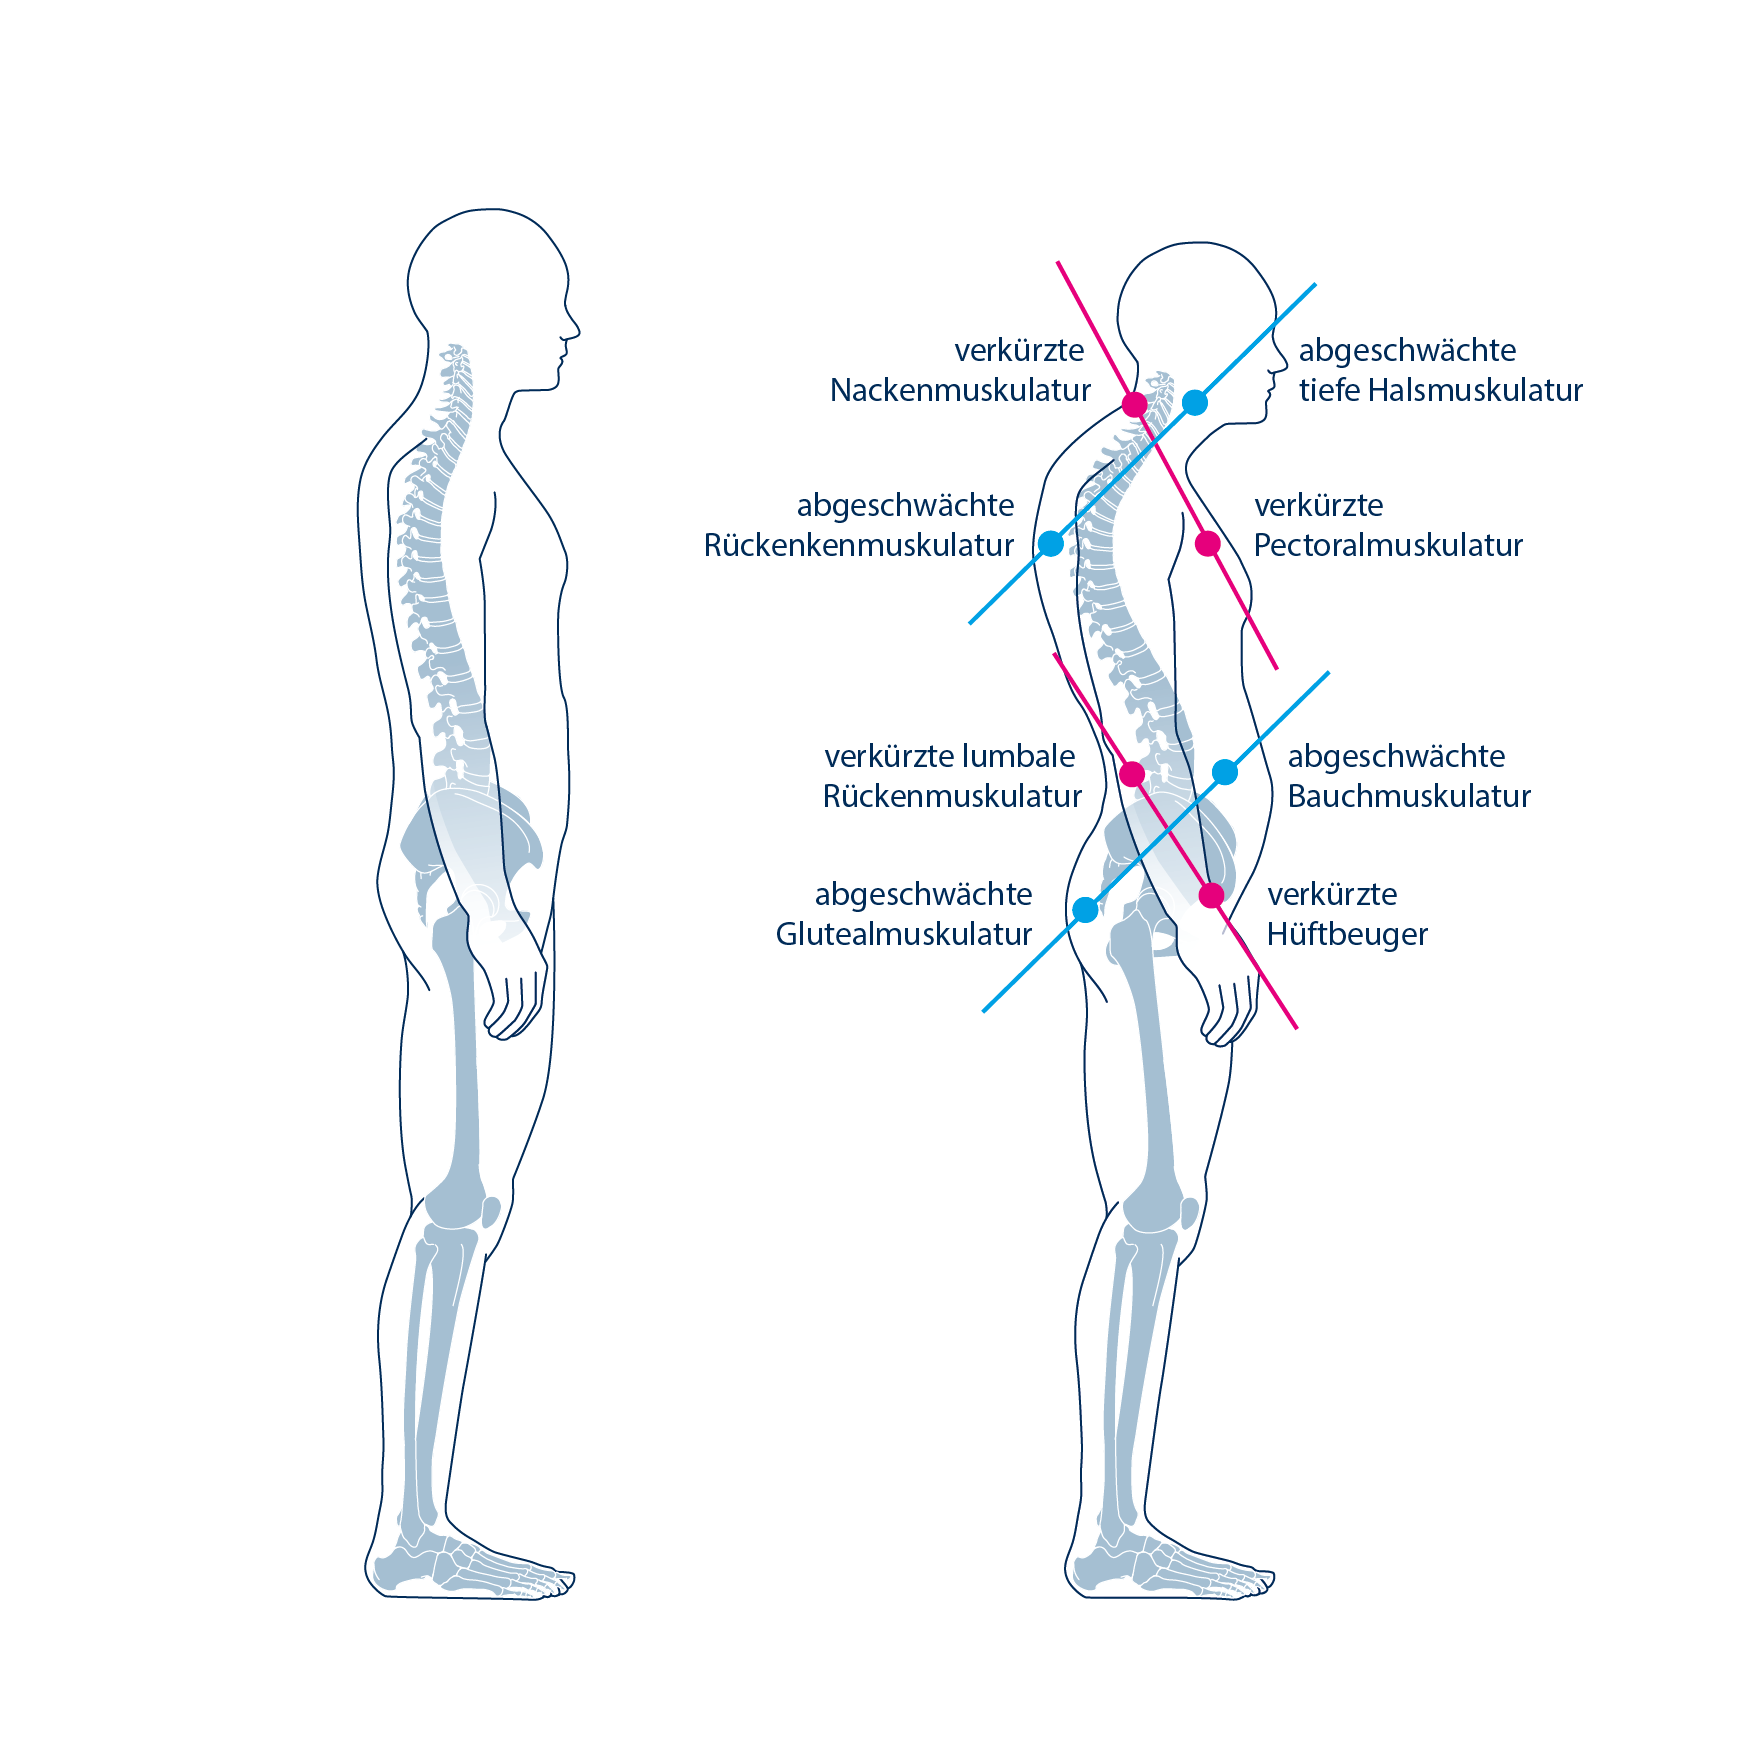

Muskuläre Triggerpunkte sind anhaltende Kontraktionen von einigen/wenigen Muskelfasern eines Muskels. Diese entstehen häufig als Reaktion einer chronischen Überlastung von Muskeln oder auch durch eine direkte oder indirekte Krafteinwirkung. Ein typisches Beispiel für eine muskuläre Überlastungssituation ist eine ungünstige Haltung am Computer – zum Beispiel beim Surfen auf einer Praxis-Homepage. Ein häufiger Mechanismus für die unfallbedingte Entstehung von Triggerpunkten ist die Überdehnung von Nackenmuskeln bei einem Schleudertrauma.